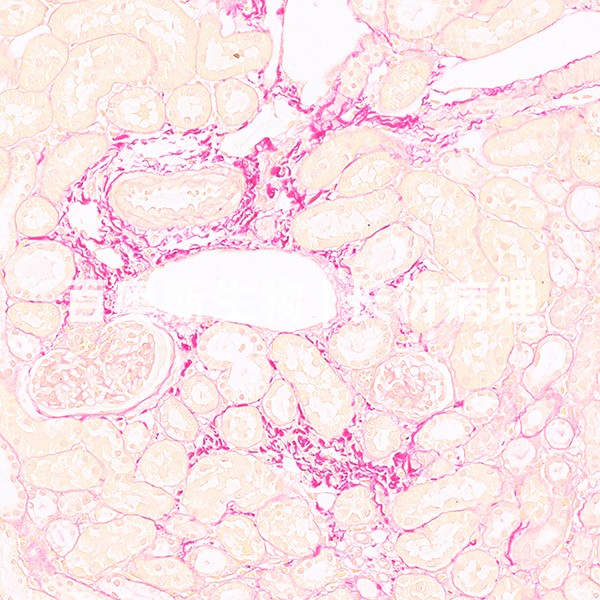

油红O染色